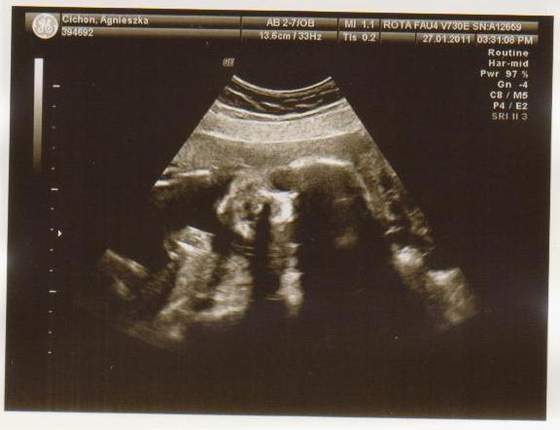

wklejam tylko zdjecia Mateuszka Tichonka na jej prośbe :-)

9a.jpg3a.JPG4a.JPG5a.jpg8a.JPG2a.JPG6a.jpg7a.JPG1a.jpg

Ło matko-jaki piękny widok na dzień dobry:)))

po raz kolejny Tichonku musze powiedziec,ze naprawdę sliczne Maleństwo się na swiat szykuje!!!